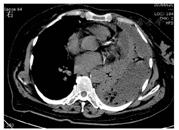

患者女,63岁,因"胸闷、发热1周"于威海市中心医院就诊,体温最高达38.5 ℃,血常规检查白细胞计数和中性粒细胞比例升高,考虑细菌感染,给予头孢克肟0.1 g(2次/d)口服抗感染治疗,服药1周后仍然高热不退,复查白细胞计数、中性粒细胞比例和CRP水平均升高,为查明病因于2019年1月10日收住入院,患者既往有多年的糖尿病和高血压病史。入院体格检查:体温为38.2 ℃,心率为130次/min,呼吸为20次/min,血压为151/79 mmHg(1 mmHg=0.133 kPa);神志清,全身浅表淋巴结未触及肿大;心律齐,各瓣膜听诊区未闻及杂音;双肺呼吸音粗,可闻及干啰音;腹软,无压痛、反跳痛,肝脾未触及,肠鸣音正常,双下肢无水肿。实验室检查:白细胞计数为28.19×109/L,中性粒细胞比例为0.96,血红蛋白为108 g/L,血小板计数为152×109/L,超敏CRP为213.7 mg/L,降钙素原为6.36 μg/L;pH值为7.45,氧分压为52.2 mmHg,二氧化碳分压为35 mmHg;AST为32 U/L,ALT为32 U/L,葡萄糖为16.9 mmol/L,总钙为2.05 mmol/L,钾为4.2 mmol/L,钠为111 mmol/L,氯为89.7 mmol/L;PT为13.9 s,纤维蛋白原为4.06 g/L,D-二聚体为4.55 mg/L。胸部CT检查示:左侧胸腔积液合并左肺膨胀不全,内见多发气体影(图1)。胸部多普勒超声检查示左侧有大量胸腔积液。为明确胸腔积液性质,并使肺复张,行胸腔闭式引流,引流液为脓性。胸腔积液常规检查示:黄色浑浊,比重为1.029,李凡他试验呈阳性,白细胞计数为93.2×109/L,中性粒细胞比例为0.92,单核细胞比例为0.08,考虑为炎性渗液。胸腔积液生物化学检查示:葡萄糖水平降低,为0.11 mmol/L,提示严重细菌感染。血培养、胸腔积液培养均显示嗜沫凝聚杆菌,为细小革兰阴性杆菌(图2)。分别接种于血平板和巧克力平板,在体积分数为0.05的二氧化碳(CO2)条件下培养72 h后有菌落生长,呈灰白色、形态细小,不溶血;在中国兰平板上无细菌生长,推测该菌为苛养菌。经德国布鲁克质谱仪鉴定及16S rRNA测序,结果均为嗜沫凝聚杆菌,且对头孢曲松、左氧氟沙星、阿米卡星、美罗培南等抗菌药物敏感。患者入院后给予哌拉西林他唑巴坦4.5 g,每8 h 1次抗感染治疗3 d,明确病原后,调整为头孢曲松(2.0 g,1次/d)联合左氧氟沙星(0.6 g,1次/d)静脉滴注,并继续行胸腔闭式引流。治疗2周后,患者双侧肺部干啰音减轻,胸闷、憋气症状较前有所改善。实验室检查示白细胞计数、CRP和降钙素原水平有所下降,抗感染治疗有效。但患者仍反复发热,胸腔脓液引流不佳,出现血流感染,经家属同意后行胸腔镜下胸膜粘连松解术,同时完善腹部超声检查,以排除其他脏器脓肿可能。应用美罗培南1.0 g(每8 h 1次)联合依替米星0.3 g(1次/d)继续抗感染治疗。胸腔镜术中诊断为左侧脓胸,患者术后无发热,胸闷、憋气症状明显改善,继续抗感染治疗2周后复查胸部CT示肺部炎症及脓液吸收较前好转(图3)。患者无发热、胸闷、憋气,双肺仅闻及少量啰音,暂停美罗培南,给予口服环丙沙星(0.5 g,2次/d)巩固治疗2周,并做好出院指导。